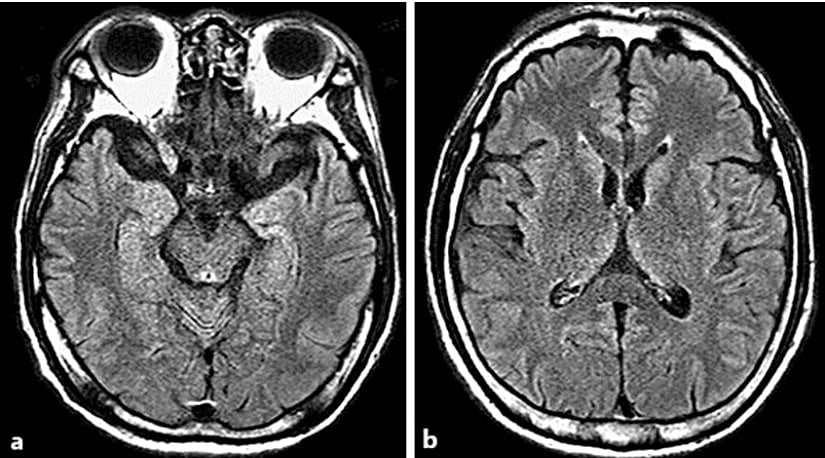

Manyetik Rezonans Görüntüleme (MRI) ve Bilgisayarlı Tomografi (CT) gibi yöntemler, beynin yapısal durumunu inceleyerek retrograd amneziye yol açabilecek nörolojik anormalliklerin belirlenmesini sağlar. Manyetik Rezonans Görüntüleme, beyin dokusundaki hasarları, tümörleri veya dejeneratif süreçleri detaylı bir şekilde görüntülerken Bilgisayarlı Tomografi, genellikle travmaya bağlı beyin hasarlarını tespit etmek için tercih edilir. Fakat bu yöntemlerin her zaman hafıza kaybının kesin nedenini ortaya koyamayacağı unutulmamalıdır.